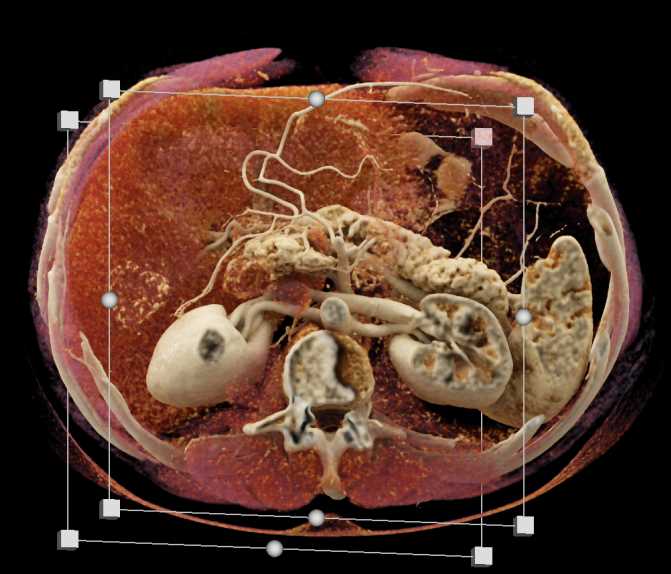

Subtle Neuroendocrine Tumor Body of Pancreas